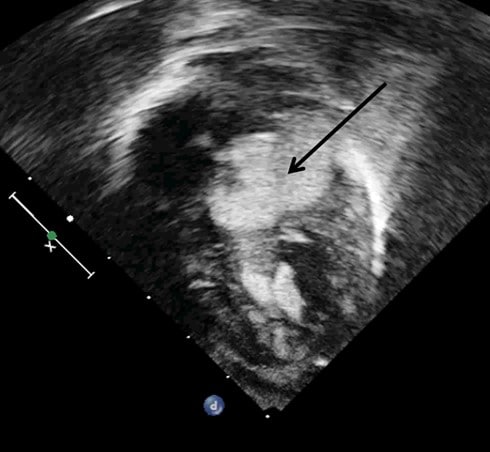

Красноярские кардиохирурги провели сложнейшую операцию новорожденному с множественными опухолями сердца

По словам врачей, из-за образований, самое большое из которых перекрывало вход в аорту, ребенок мог погибнуть в любой момент. Такая патология встречается у детей крайне редко — в 1 случае на 10 000.

Маленького пациента в Федеральный центр сердечно-сосудистой хирургии Красноярска доставили из Хакасии. Необходима была ювелирная точность хирургов, каждое движение могло стать для ребенка фатальным.

В итоге операция прошла успешно, жизни малыша сейчас ничего не угрожает. Ему предстоит долгое наблюдение за остальными опухолями сердца, но теперь у ребенка есть все шансы на жизнь. Новый год маленький пациент встретит дома, в кругу семьи.